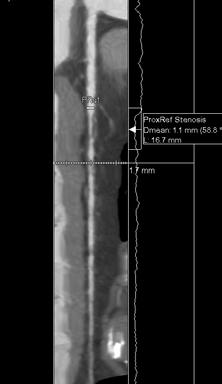

Conceptul de placă de aterom vulnerabilă – cum este integrat în noua paradigmă de stratificare a riscului de eveniment coronarian acut și care este rolul examinării CT coronariene

Dr. Ofelia Niță